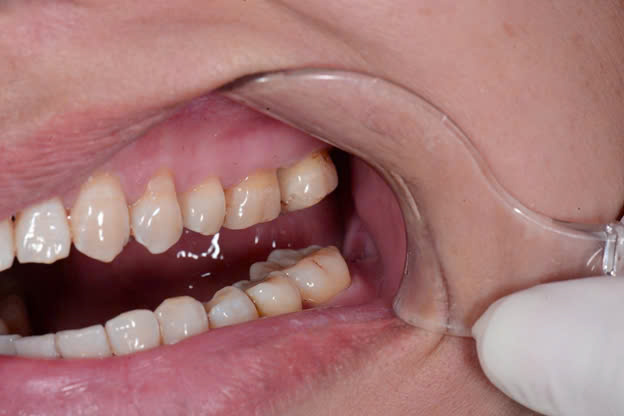

Bước 1: Đặt chun tách khe

Bước 2: Tháo chun, làm sạch và tạo xoang trám bằng kỹ thuật đường hầm